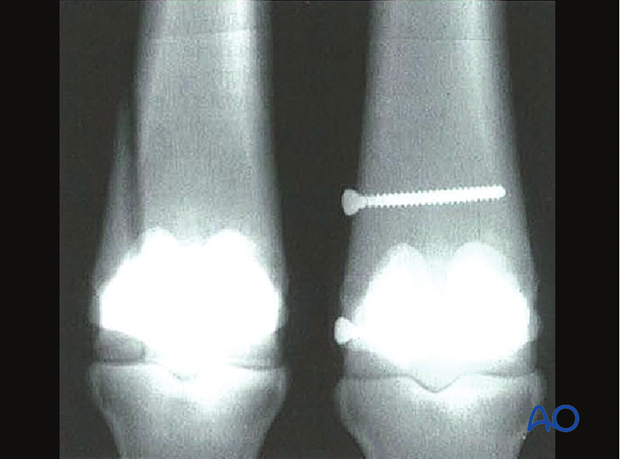

Metacarpal/-tarsal condyles: Description and preoperative considerations